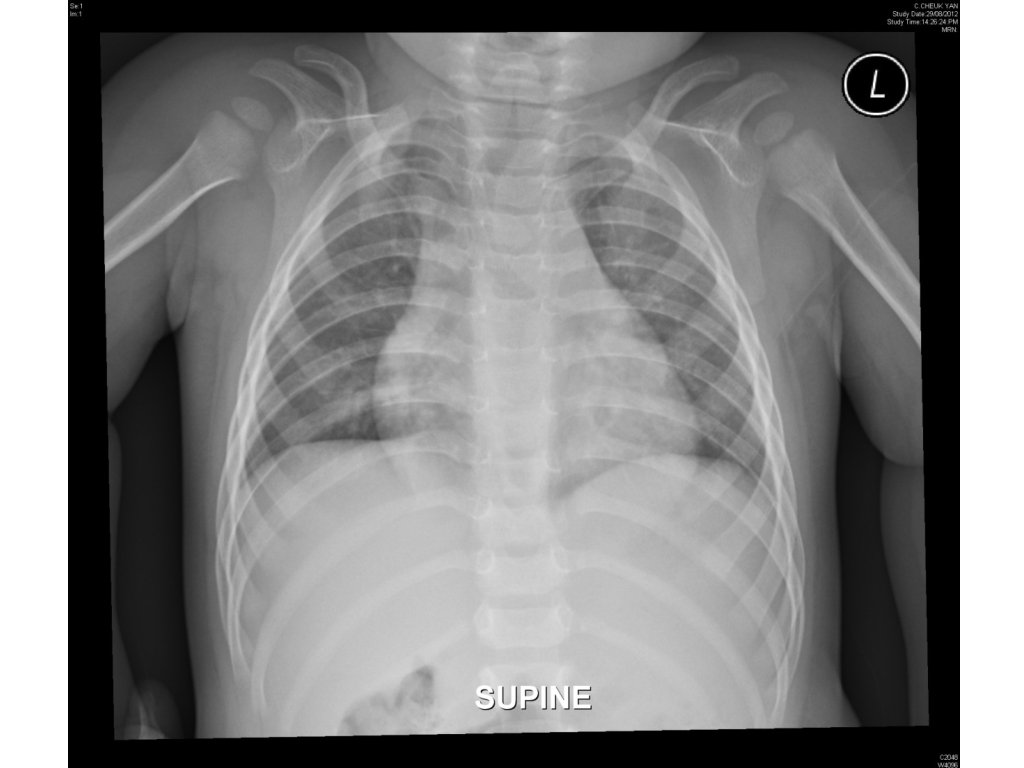

Case 2 • 13 months/M • Cough for 3 days • Noisy breathing for a day

1. Name 2 CXR findings. Are they pathological? • Steeple sign (subglottic tracheal narrowing) - pathological. • Right deviation of trachea – normal variant. 2. Name 3 neck X-ray findings. 3. What is the diagnosis? 4. Name 2 medications for the disease.

1. Name 2 CXR findings. Are they pathological? • Steeple sign (subglottic tracheal narrowing) - pathological. • Right deviation of trachea – normal variant. 2. Name 3 neck X-ray findings. • Prevertebral soft tissue swelling, subglottic tracheal narrowing, ballooning of hypopharynx 3. What is the diagnosis? 4. Name 2 medications for the disease.

1. Name 2 CXR findings. Are they pathological? • Steeple sign (subglottic tracheal narrowing) - pathological. • Right deviation of trachea – normal variant. 2. Name 3 neck X-ray findings. • 3. Prevertebral soft tissue swelling, subglottic tracheal narrowing, ballooning of hypopharynx What is the diagnosis? • 4. Croup Name 2 medications for the disease. • Dexamethasone (po/IM/IV) • Nebulized Adrenaline